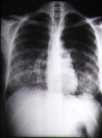

Material y Métodos: El número de reconocimientos médicos efectuados en la ciudad de Barcelona en 1998 fue de 1513, la muestra que pudimos tomar para la realización de un Mantoux fue de 476 (31.4%). En este estudio descriptivo de prevalencia se consideraron como factores de riesgo en la recogida de datos las variables de: edad, sexo, distrito de residencia, nacionalidad, antecedentes personales de tabaquismo, alcoholismo, adicción a otras drogas y VIH. A los casos Mantoux (+) se les practicaba sistemáticamente radiografías de tórax (frente y perfil), en caso de que presentaran lesiones compatibles o tuvieran factores de riesgo se les enviaba al Centro de Enfermedades del tórax para valoración. Se revisaron los contactos a bordo de los casos índice detectados.

Fueron positivos 223 casos (48,84%), a éstos se les practicó una radiografía de Torax (frente y perfil) presentando lesiones compatibles con proceso tuberculoso 6 casos, que fueron enviados al Centro de Enfermedades del Tórax junto con 2 casos más ( Mantoux + y Rx -) que por edad y según el protocolo establecido debían ser estudiados.